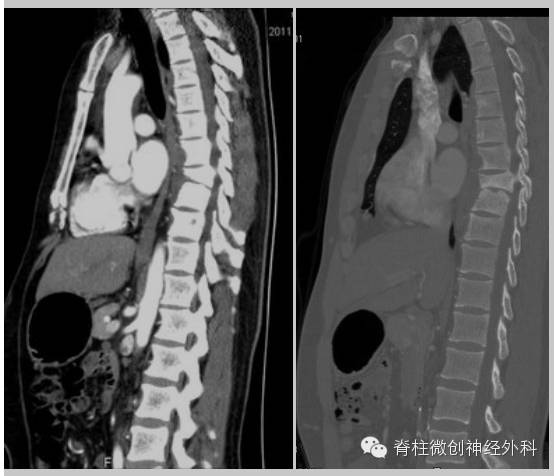

影像学(CT)检查资料:

影像学资料解读:胸椎多椎体骨破坏、椎旁脓肿广泛、死骨形成。